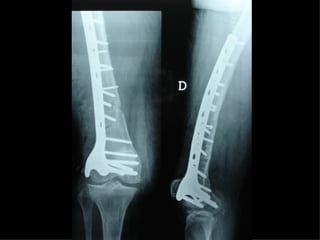

INDICAZIONI COMUNI Fratture sovracondiloidee Fratture intercondiliodee Fratture diafisarie distali PARTICOLARI Fratture con grave osteoporosi Fratture periprotesiche

VANTAGGI CHIRURGIA MININVASIVA Mini Open Inserimento della placca sottocutaneo per scivolamento Viti percutanee Preservazione dei tessuti molli Ridotto danno vascolare Rapida ripresa funzionale

F, 68 y